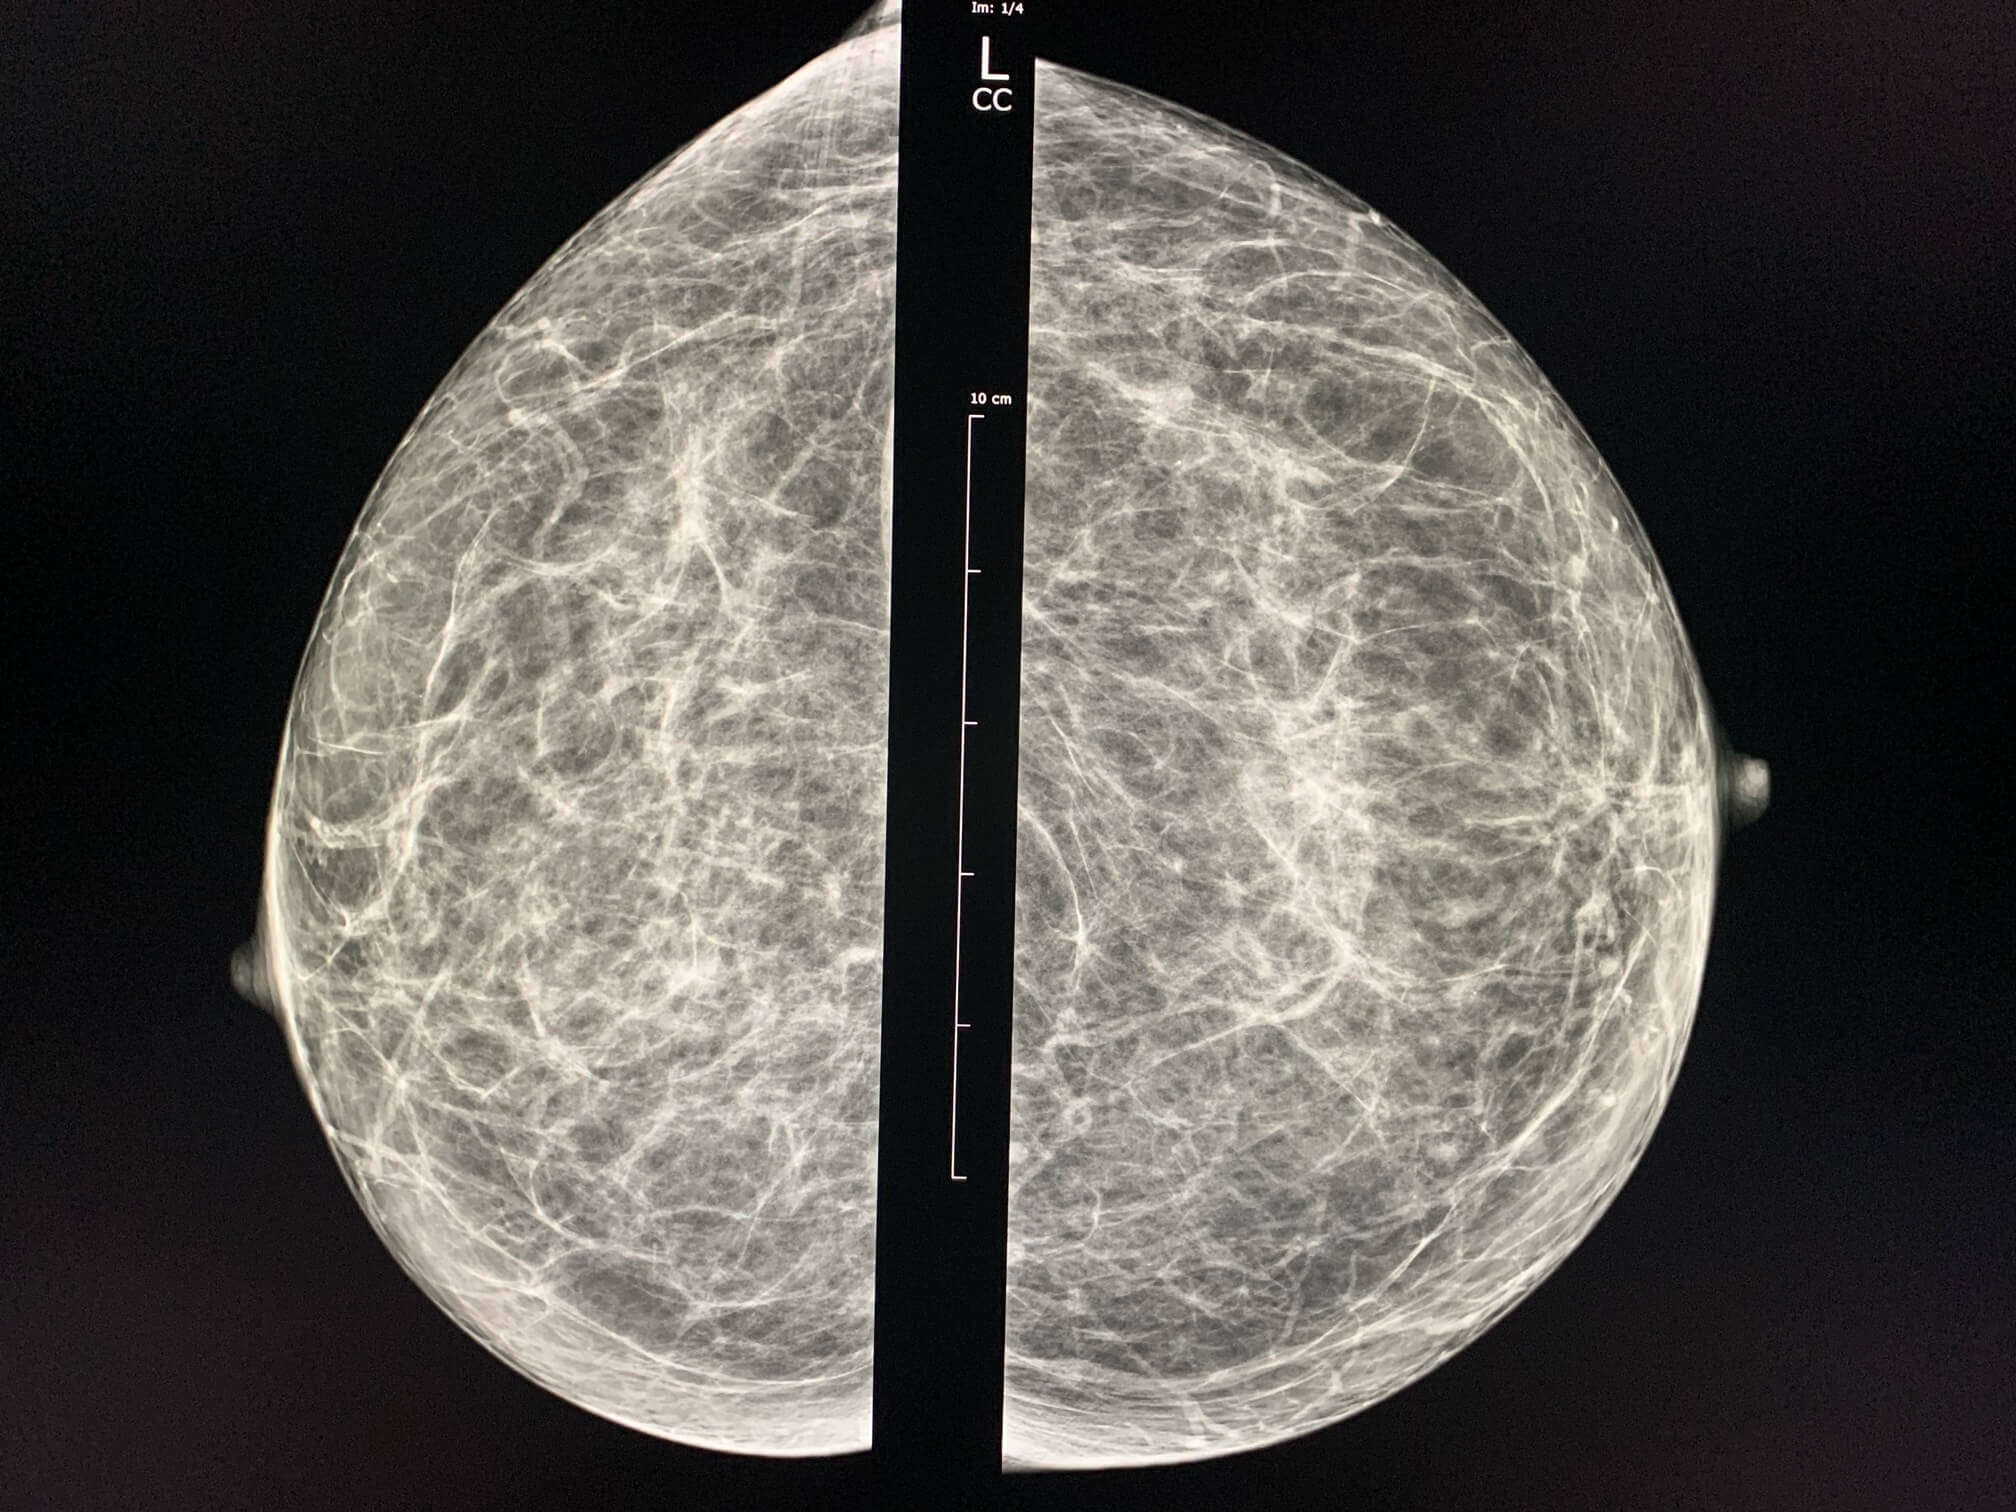

65-year-old patient comes for screening mammography.

MammoScreen™ points to a lesion in the superolateral quadrant of the left breast.

Ultrasound and biopsy confirm invasive carcinoma SBR II, RH+, HER2-

In retrospective, the MammoScreen’s analysis of the 2018 mammogram points to the same lesion on the left oblique image. Moreover, this exam has been interpreted as normal by two readers (in France all cases considered negative are read by a second reader)